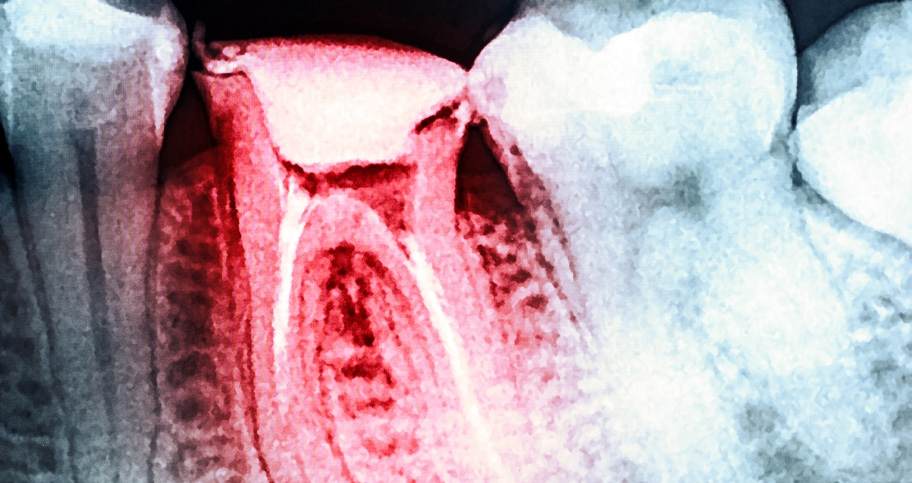

Dr. Brüsehaber: Eine der größten Herausforderungen stellt die substanzschonende Darstellung der Wurzelkanaleingänge dar, wenn die Pulpakammer obliteriert ist. Sollte ich während der Präparation der primären Zugangskavität die Pulpakammer nicht direkt mit meinem Instrument darstellen können, habe ich möglicherweise Probleme, mich zu orientieren.

Dr. Brüsehaber: Oft sind Wurzelkanäle nicht sofort penetrierbar. In einer solchen Situation kann wiederum der EndoTracer zum Einsatz kommen. Ich beginne mit der Größe 008, den sichtbaren Kanalstrukturen folgend in die Tiefe zu präparieren, und wechsele im weiteren Verlauf zur Größe 006. Obliterierte Kanaleingänge und Isthmen lassen sich auf diese Weise mit dem EndoTracer sehr gut im trockenen Zustand und unter direkter Sicht ausarbeiten.

Dr. Brüsehaber: Den EX2 setze ich als Alternative zum EndoTracer zur initialen Gestaltung der Zugangskavität und zur Darstellung der Kanaleingänge ein. Mit ihm lassen sich auch Dentinüberhänge im Bereich des Wurzelkanaleingangs leicht abtragen. Der EX1 kann im weiteren Behandlungsverlauf zum Einsatz kommen, um Isthmen zwischen den Kanälen darzustellen. Letztendlich ist das aber alles eine Frage der individuellen Anatomie des Zahnes. Es gibt kein allgemeines „Kochrezept“. Ziel ist immer ein kontrollierter Substanzabtrag (Abb. 5 und 6).